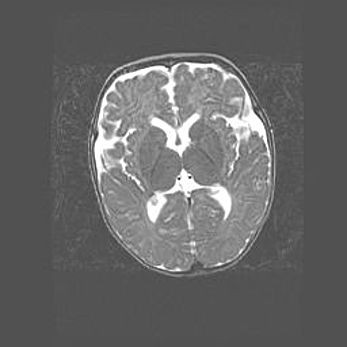

Множественные кисты обоих полушарий головного мозга, наибольшая из них в правой затылочной области. Ассиметричная атрофическая гидроцефалия.

Возраст: 7 месяцев

Вес: 5660 г

Пол: мужской

Окружность головы: 41,5 см

Срок гестации: 28-29 недель

Кисты головного мозга развиваются в результате многоочаговых некрозов вещества мозга и возникают вследствие перенесенной перинатальной инфекции, менингитов, энцефалитов, асфиксии, родовой травмы, расстройств мозгового кровообращения различного генеза. Образованию кист в веществе головного мозга плодов и новорожденных способствуют такие факторы, как высокое содержание в нем воды, недостаточная (или отсутствие) миелинизация и слабая астроглиальная реакция на повреждение.

Кисты могут сочетаться с гидроцефалией и другими поражениями головного мозга.